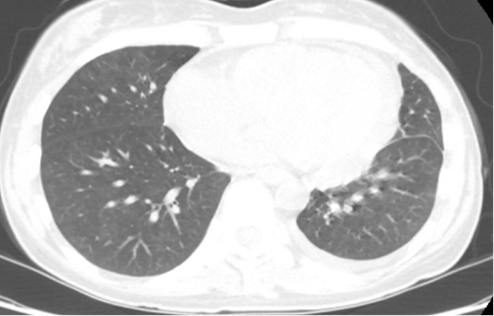

Follow-up CT chest showed significant improvement in the bilateral pneumonia. Repeat serum protein electrophoresis showed resolution of the monoclonal gammopathy, supporting a transient MGUS likely related to the acute CMV infection.

Figure 3: CT chest showing improved pericardial effusion and lung infiltrates.